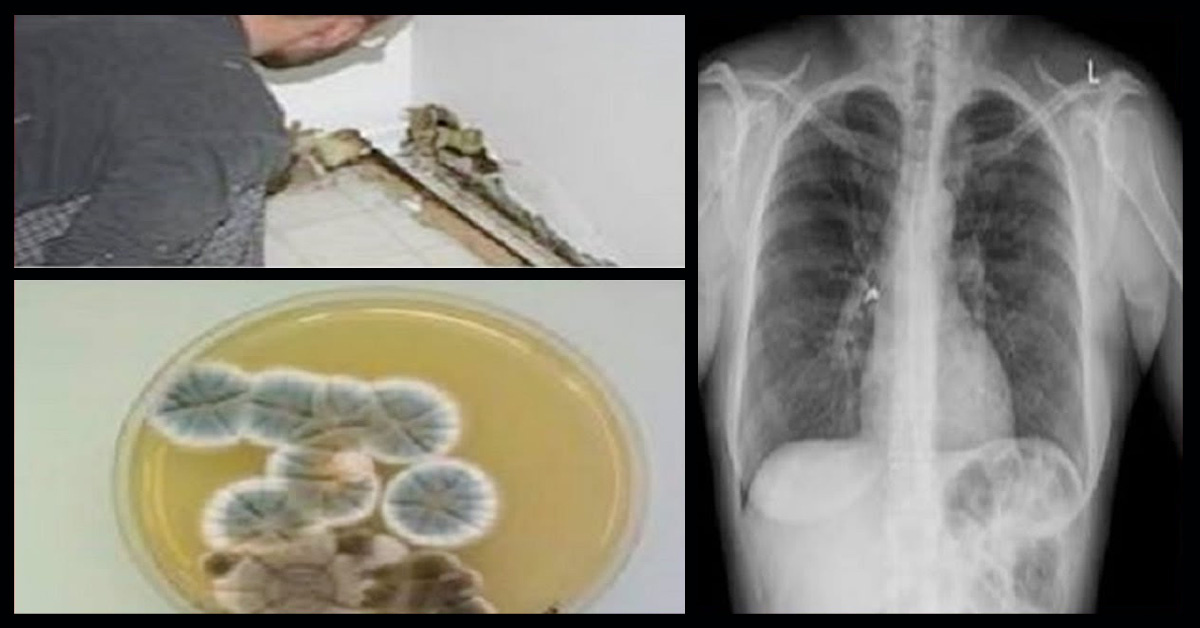

Apesar de não ter cheiro ou ser visível a olho nu, este fungo pode estar aglomerado e crescendo em sua casa. Este pode ser o motivo de você se sentir doente. Sua saúde pode estar sendo afetada por envenenamento por mofo.

O mofo se prolifera em locais úmidos, podem surgir em qualquer canto da casa, nas paredes.

O mofo é formado por vários fungos, que crescem em filamentos e se reproduzem, formado minúsculos esporos que se espalham no ar e são invisíveis a olho nu.

É um problema tão sério que pode afetar até mesmo o nosso sistema nervoso central. Os sintomas mais comuns causados por contato ao mofo são olhos vermelhos, irritação na garganta, irritação na pele (coceiras, vermelhidão), tosse, crises de rinite, sinusite crônica, entre outros problemas respiratórios. Tem sido associado também, hemorragias pulmonares, insuficiências do sistema imunológico, fadigas, dores de cabeça e variações de humor.

A ‘doença do mofo’ está associada a ‘síndrome do edifício doente’, isto é uma inflamação sistêmica após contato com propriedades contaminadas com organismos toxigênicos.